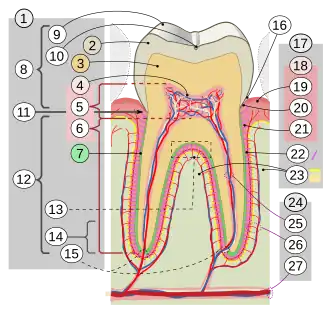

Dente é uma estrutura localizada na boca que é dura, saliente e esbranquiçada composta por polpa, dentina e esmalte que é originada no maxilar e na mandíbula (ou arcada dentária no ser humano) de muitos vertebrados.[1] É usado para cortar, prender e triturar alimentos, preparando-os para serem deglutidos.

Um humano adulto tem normalmente 32 dentes, dezesseis na mandíbula e dezesseis na maxilar. Os quatro incisivos, localizados à frente, cortam pedaços de comida não muito duros. Junto deles, estão os dois caninos, um de cada lado (sendo quatro no total). Por serem pontiagudos, servem para dilacerar e perfurar. Os incisivos e os caninos preparam uma quantidade de alimento para serem deglutidos. Os quatro pré-molares e os seis molares cumprem as funções de o cortar, esmagar e triturar.

Os dentes se unem ao osso alveolar (alvéolo de sustentação), por meio do ligamento periodontal, em uma articulação denominada Gonfose. As articulações fibrosas, como as gonfoses, caracterizam-se por unir os ossos através de tecido conjuntivo fibroso, permitindo pouco ou nenhum movimento.